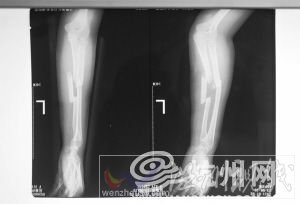

武警医院骨科X光片显示:吴菊萍左手臂的尺桡骨断成了三截,有骨头断端戳出皮肤出来,伤势非常严重,需要立即手术。

富阳市中医骨伤医院主管吴菊萍的医生叫裘晓东。裘医生说,“她伤得很重,手臂受到了巨大撞击后产生爆裂伤。我们医院金登峰副院长刚从外地回家,他得知消息立刻赶到医院,组织专家为吴女士会诊。”

“尺桡骨是人手臂中最精巧的一根骨头,不仅起支撑的作用,还负责手臂旋转功能。这根尺桡骨,最细的地方大概是1.5厘米,最粗的地方是4厘米左右。”金登峰说。

吴女士的伤势在尺桡骨骨折中算非常严重的。

不过金副院长说,富阳市中医骨伤医院的骨伤疗法已经传了150年,每年治疗2000多例尺桡骨骨折患者,有信心把吴女士治好。

目前,估计需住院3周。基本恢复要3个月,彻底好要半年以上。金副院长估计,治疗费在5万左右,“我们医院帮她全部免掉。”